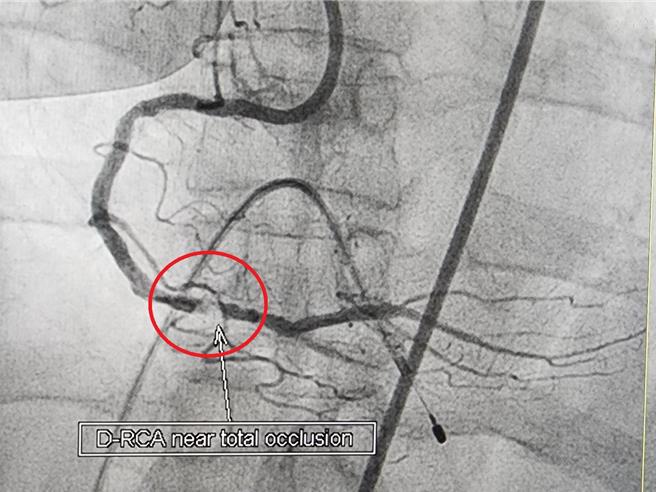

62岁的邱女士患有高血压、高血脂、末期肾病,并定期接受血液透析。近期出现间歇性胸闷,经检查发现右冠状动脉钙化严重狭窄,传统气球无法处理。经1个月药物治疗无效后,使用心导管冠状动脉旋磨治疗术成功解决病灶并顺利置放支架。邱女士术后恢復良好,这是苗栗县首例成功使用此技术的案例。

邱女士在接受心导管冠状动脉摄影检查后,发现右冠状动脉钙化严重,并且存在无法通过的狭窄病灶。儘管经过一个月的药物治疗,她的症状依然未见改善,最终转向心导管冠状动脉旋磨治疗术进行处理。这项技术搭配血管内超音波,成功去除了钙化病灶,并顺利置放支架。